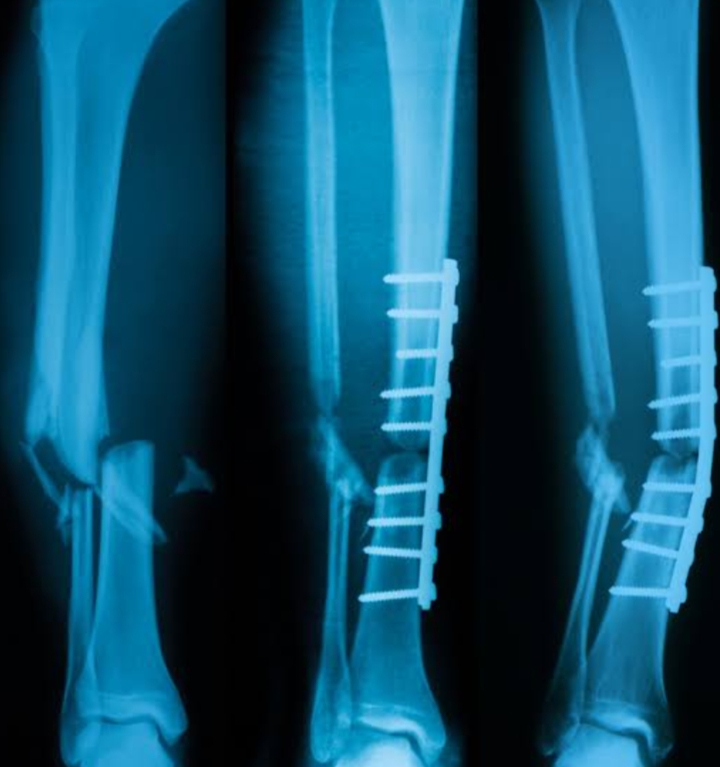

People who smoke are more likely to experience delayed healing, nonunion (failure of the bone to heal), and infections after injury or surgery.

Scientific studies have found that smokers often take longer to recover from fractures than non-smokers. In addition, surgical outcomes—such as bone grafts or spinal procedures—tend to be less successful in smokers.